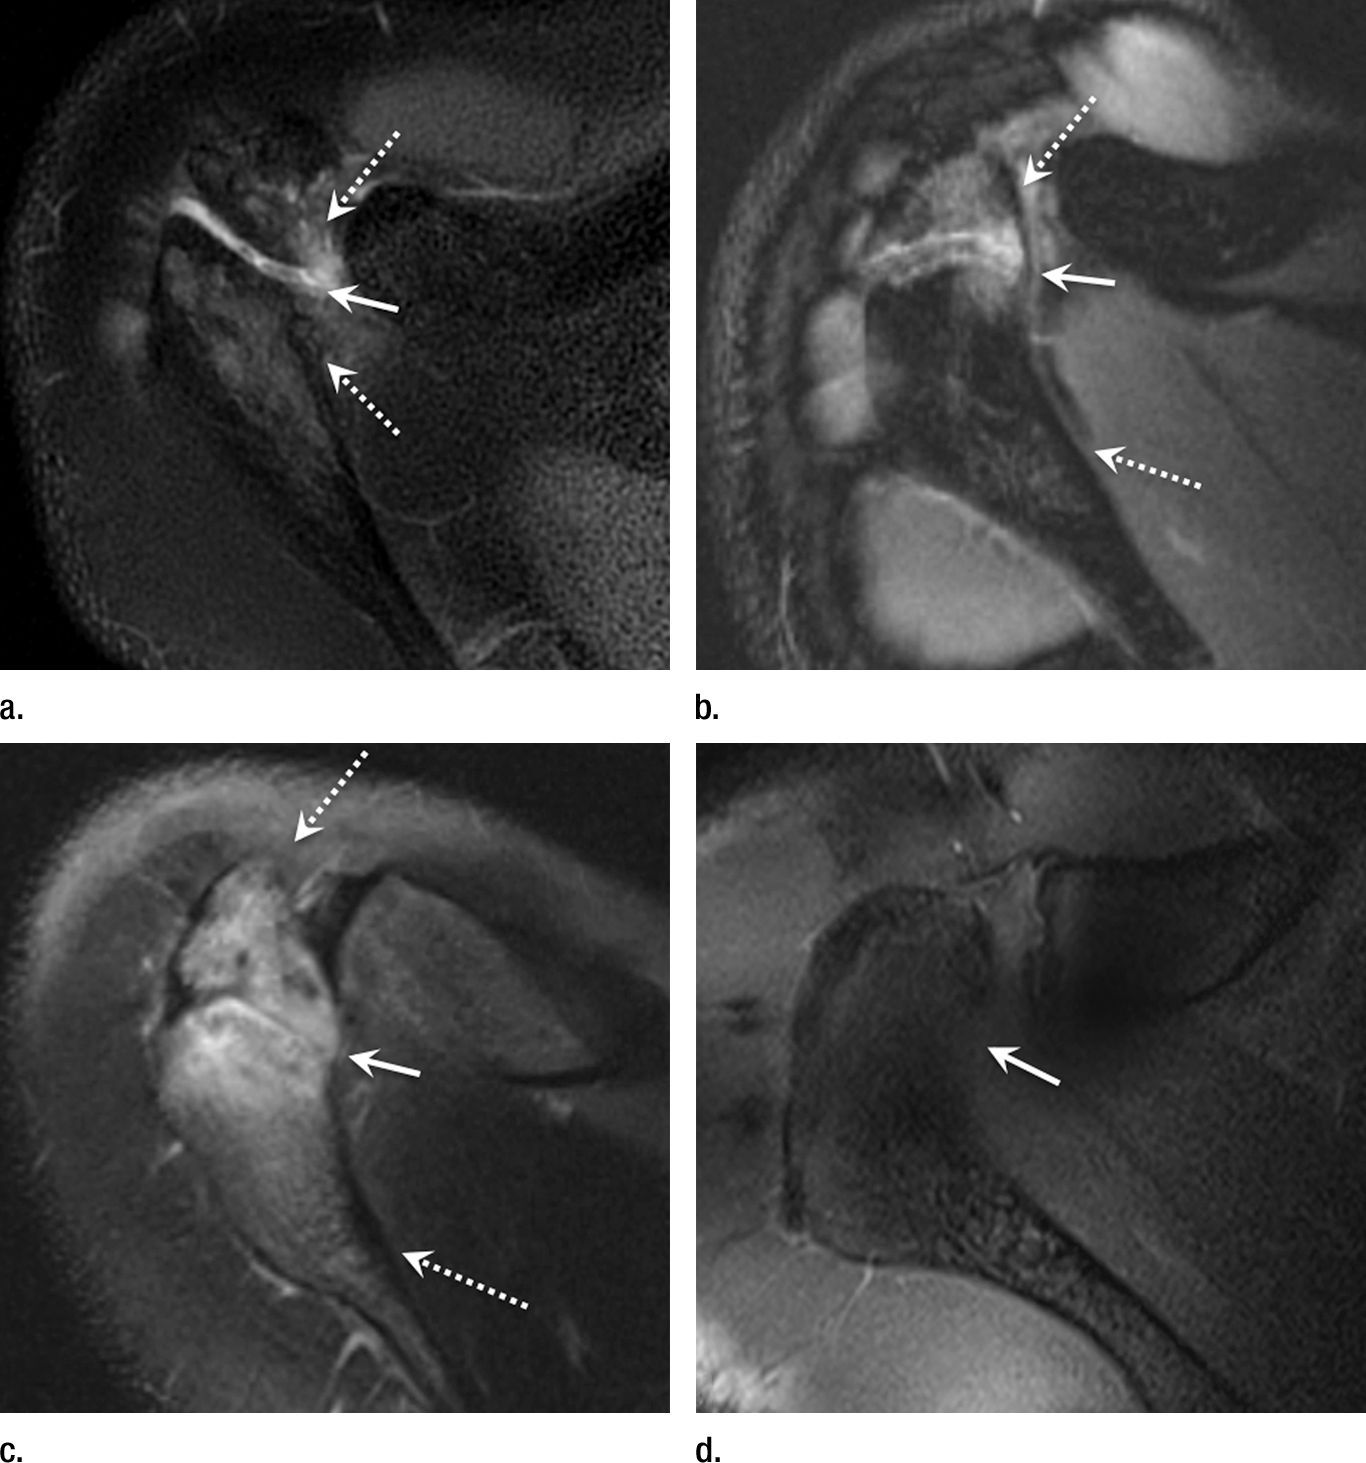

MR Imaging and MR Arthrography of Paraglenoid Labral Cysts AJR

From www.ajronline.org

MR Imaging and MR Arthrography of Paraglenoid Labral Cysts AJR Mlb Pitchers Labrum Surgery Less well known than ucl tears—the injury. Reported on 42 mlb pitchers with surgically treated isolated glenoid labral tears with 69% returning to play in at least 1 season and 29% at 3 seasons after. labral tears are, thankfully, relatively uncommon in major league baseball. flagler currently has two baseball players who are dealing with the aftermath of. Mlb Pitchers Labrum Surgery.